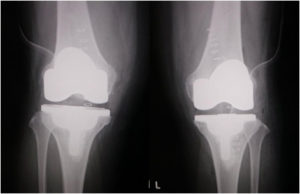

変形性膝関節症(両側同時人工膝関節置換術)

手術後